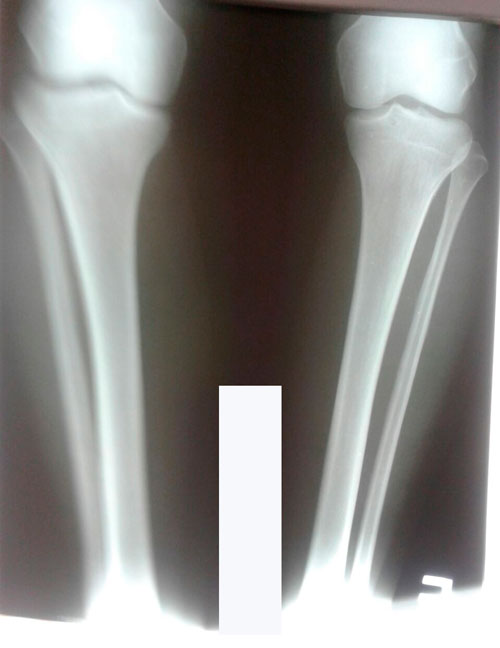

Re: Олимпиада

Дата операции 26.04.2018г.

Дата снятия аппаратов 02.08.2018г.

Срок сращения 95 дней.